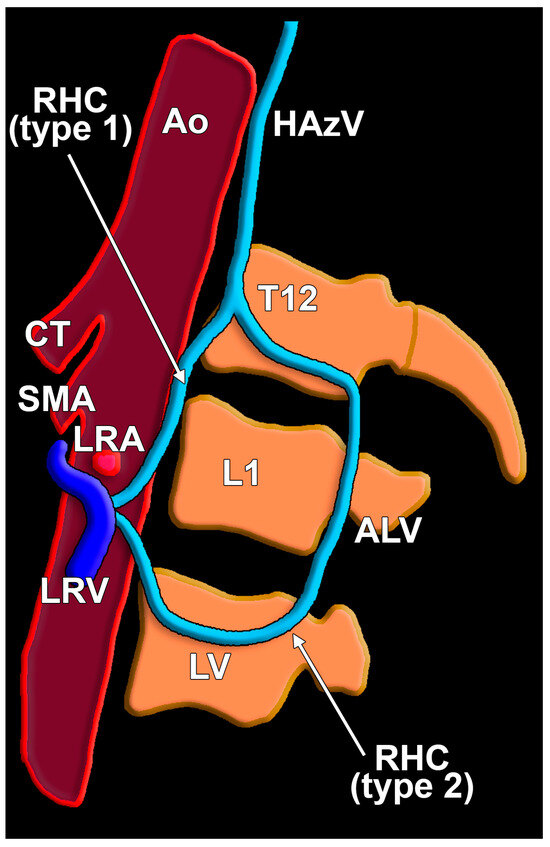

| ALV | ascending lumbar vein |

| HAzV | hemiazygos vein |

| LRV | left renal vein |

| RHC | reno-hemiazygos connection |

| Type 1 | Type 2 | |

|---|---|---|

| M | 2/4 (50%) | 2/4 (50%) |

| 2/85 (2.35%) | 2/85 (2.35%) | |

| F | 9/10 (90%) | 1/10 (10%) |

| 9/65 (13.84%) | 1/65 (1.53%) |

| L1/L2 Disc | L2 | L2/L3 Disc | L3 | |

|---|---|---|---|---|

| Type 1 (11 cases) | 1 (9.09%) | 5 (45.46%) | 3 (27.27%) | 2 (18.18%) |

| Type 2 (3 cases) | – | 1 (33.33%) | – | 2 (66.67%) |